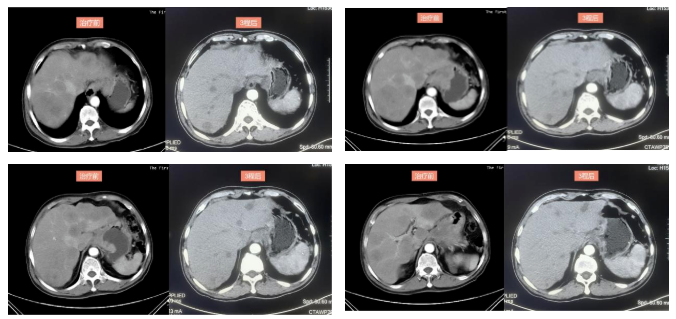

2022-4-13复查上腹部CT(3疗程后):符合贲门-胃体癌表现,伴肝内多发转移瘤,病灶均较前明显缩小,疗效评价PR。

该患者初诊为HER2阳性晚期胃癌伴肝、淋巴结多发转移,临床分期为cT4N2M1 Ⅳ期,分子病理检测结果为MSS、PD-L1阴性(CPS=0)。根据2021版CSCO胃癌诊疗指南推荐,晚期HER2阳性患者,1A推荐曲妥珠单抗联合奥沙利铂/顺铂+5-FU/卡培他滨方案。基于KEYNOTE-811研究的初步疗效数据,美国FDA在2021年5月份,就已加速批准帕博利珠单抗联合曲妥珠单抗+化疗,一线治疗HER2阳性胃/胃食管连接癌的适应证。针对本例患者,为了追求更有效的治疗效果,尝试使用曲妥珠单抗、PD-1单抗联合化疗治疗,3周期后影像学评估PR,疗效显著,不良反应可控,说明曲妥珠单抗(汉曲优)联合抗PD-1单抗治疗的疗效显著及安全性良好。

本病例中,患者为HER2阳性、MSS、PD-L1阴性(CPS=0)晚期胃癌,为了追求更好的治疗效果,参考KEYNOTE-811研究的治疗方案,结合患者的分子病理特征与实际情况,患者最终治疗方案为曲妥珠单抗(汉曲优)+PD-1单抗+卡培他滨+奥沙利铂。治疗3个疗程后,患者肿瘤标志物降至正常,影像学疗效评价PR。治疗过程中仅观察到胃肠道反应,心脏、肝肾功能毒性及免疫治疗相关毒性均未出现,安全性可控。结果证明汉曲优在HER2阳性晚期胃癌患者治疗上疗效显著,安全性良好,临床上可以替代使用。